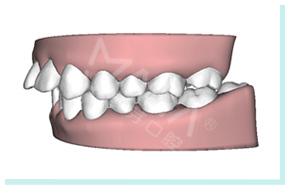

推磨牙后移等减少拔牙

重塑正确咬合关系

解决各类牙齿畸形